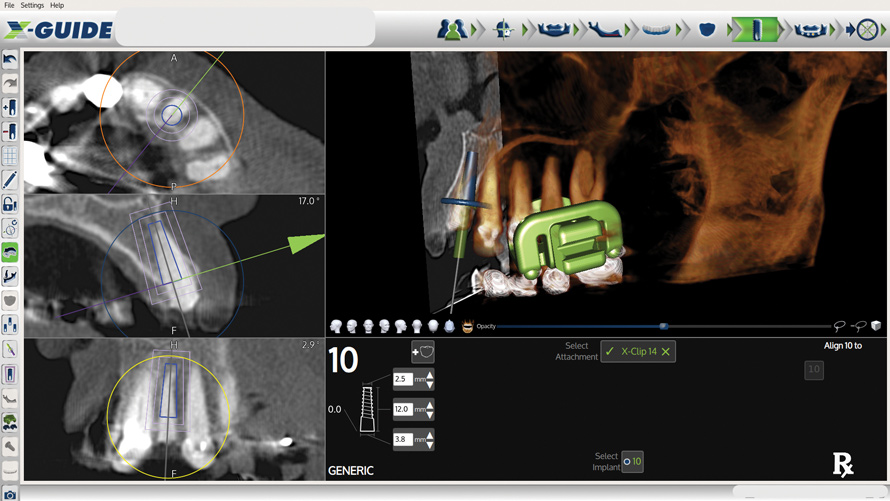

After clinical evaluation, CBCT assessment with a dynamic navigation fiducial was followed by planning for immediate implant placement. This included evaluation of inferior alveolar nerve position, undercut, buccal plate dehiscence, implant positioning in the defect, and retention screw path. The patient was taken to surgery under intravenous and local anesthesia with removal of the mandibular right second and third molar teeth. The sites were aggressively debrided with a mesiobuccal root dehiscence noted, and site development followed with the use of dynamic navigation (Figure 13).

Fig 13. Screenshot of dynamic navigation preparation.

Figure 13